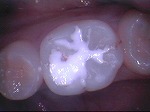

ドックスベストセメント

~ドックベストセメント処置~

~グラスアイオノマー仮封~

~CR充填~